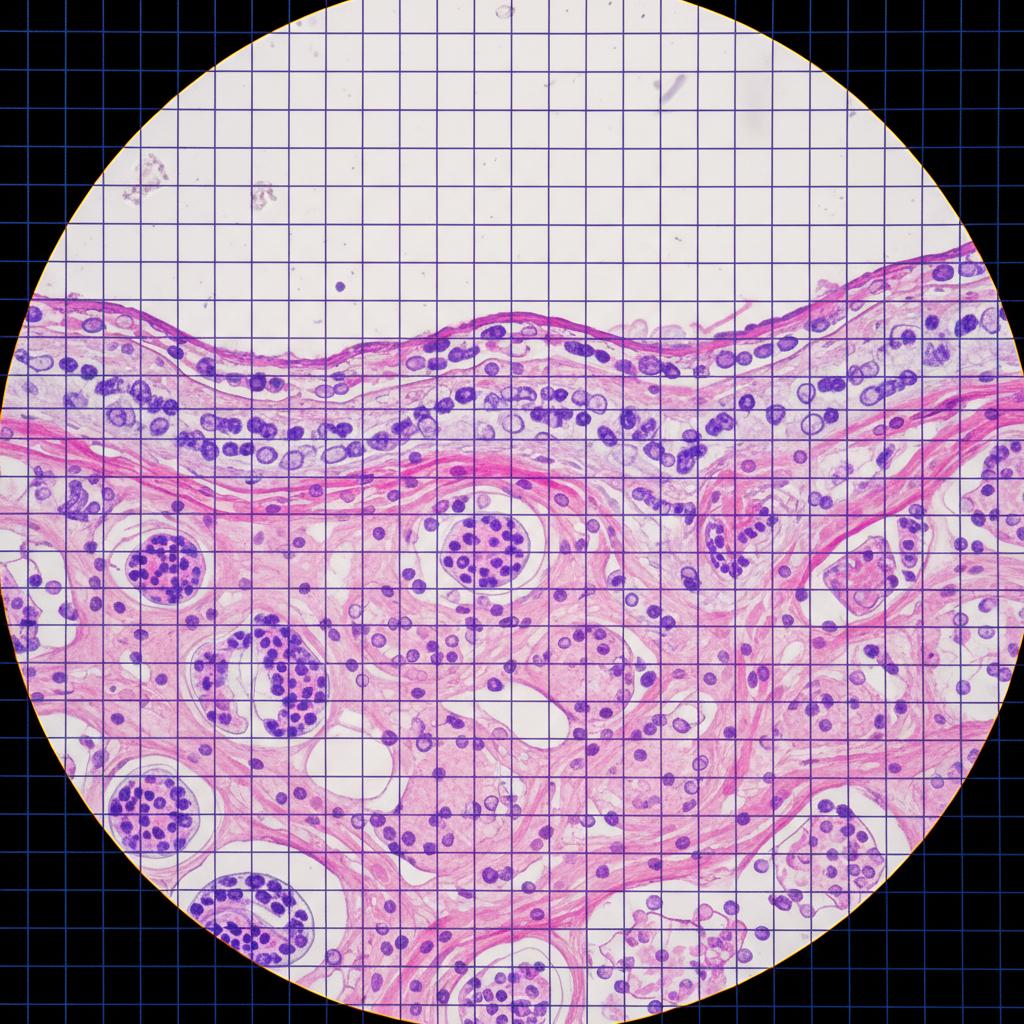

- Próbka trafia do laboratorium histopatologicznego, gdzie jest odpowiednio przygotowywana (utrwalanie, zatapianie w parafinie).

- Materiał jest krojony na cienkie skrawki (2-5 mikrometrów) i barwiony specjalnymi barwnikami.

- Doświadczony histopatolog analizuje preparat pod mikroskopem, oceniając strukturę tkanek i cechy komórek.

- Wynik jest sporządzany w formie opisu, często z zaleceniami dotyczącymi dalszego postępowania.

Cały proces trwa zwykle od 7 do 21 dni, ale w skomplikowanych przypadkach może się wydłużyć.